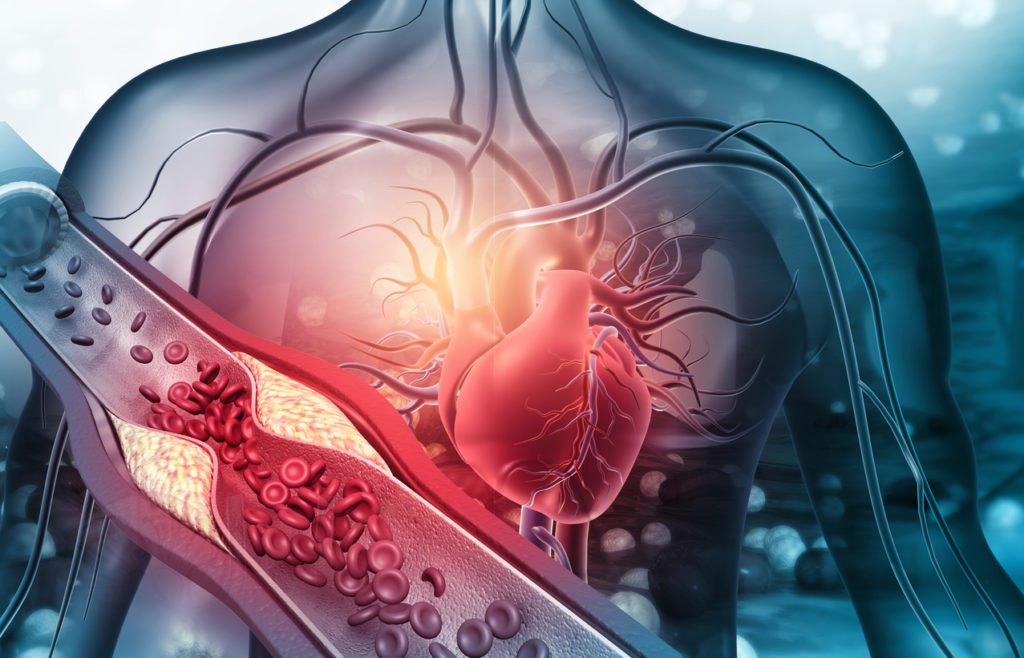

Coronary Artery Bypass Grafting (CABG) is a surgical procedure performed to treat blocked coronary arteries. A healthy blood vessel from the body is grafted to bypass the blocked artery, improving blood flow to the heart muscle and reducing cardiac risk.

Vascular Surgery

The vascular system, made up of arteries and veins, is essential for proper blood circulation. Problems like aneurysms, blockages, or varicose veins can seriously affect overall health. Vascular surgery addresses these conditions by restoring normal blood flow and preventing future complications. Dr. Pradeep Pokharna uses modern surgical techniques to treat vascular problems with accuracy and care, helping patients regain mobility, energy, and confidence in their daily life.